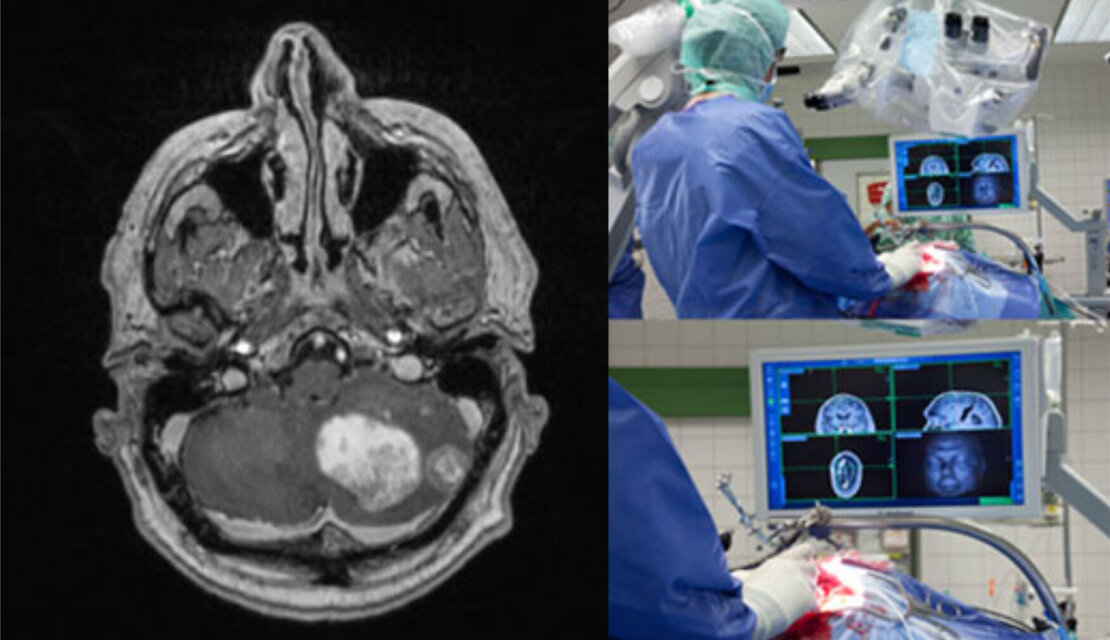

Für eine präzise Diagnose sind die neurologische Untersuchung und die Bildgebung (z. B. Kernspintomographie) wichtig. Diese Bilder können auch während der Operation zur Neuronavigation benutzt werden, um den Tumor und umliegende Hirnstrukturen genau lokalisieren zu können. Je nach genauer Lokalisation können auch weitere Untersuchungen nötig werden, wie z. B. audiometrische Untersuchungen bei Tumoren, die in der Nähe des Hörnervs (Nervus vestibulocochlearis) lokalisiert sind.

Die Behandlung ist in der Regel zunächst chirurgisch, d. h. es wird die möglichst vollständige operative Entfernung des Tumors angestrebt. Dies gelingt bei Tumoren, die in lebenswichtige Strukturen einwachsen, nicht immer radikal. In der modernen Schädelbasis-Chirurgie gewinnt das Endoskop zunehmend an Bedeutung und wird immer häufiger für verschiedene Erkrankungen eingesetzt. Neue Endoskop-Generationen ermöglichen dem Neurochirurgen, diese Instrumente und ihre exzellente Lichtqualität und optische Auflösung während mikrochirurgischer Operationen zu nutzen. Die Kombination dieser Vorteile wird als „endoskopisch-assistierte Mikrochirurgie“ bezeichnet.